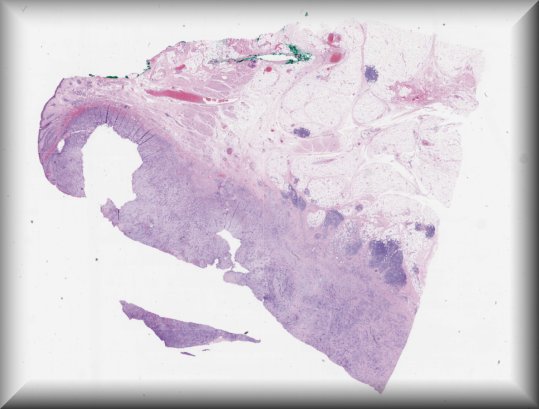

Thomas J. Cummings (Durham, North Carolina): 54-year-old male with multiple systemic infections underwent enucleation after 2 months of pain, redness and acute loss of vision. |